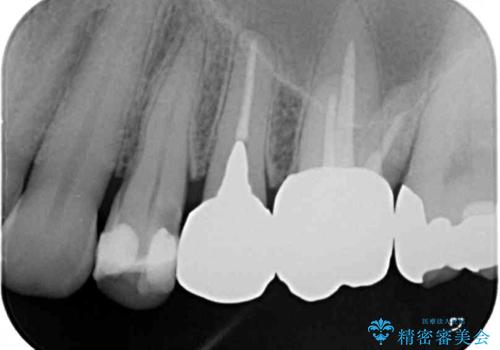

精査の結果、詰め物の下に虫歯が大きく広がっているのがわかりました。

外見からはあまり大きな虫歯があるようには見えなくても、X線検査をすることで、詰め物の下に虫歯が広がっていることは多々あります。